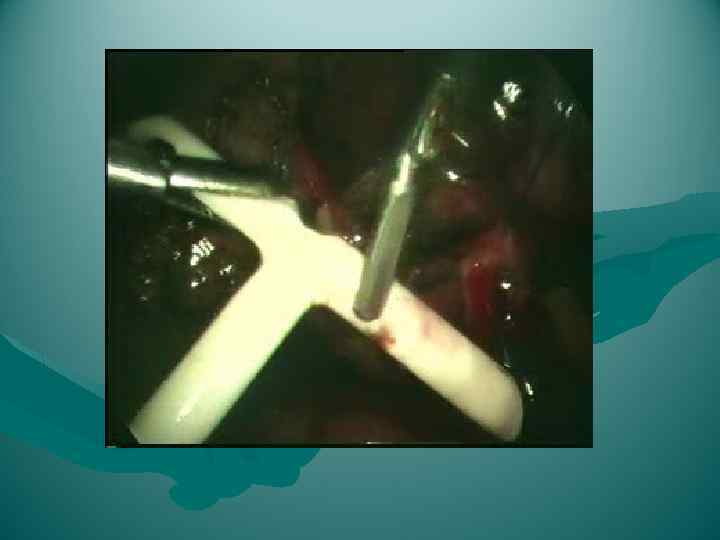

Гепатэктомия у реципиента: сохранение нижней полой вены

Гепатэктомия у реципиента: сохранение нижней полой вены

Родственная трансплантация правой доли печени Имплантация: гепатико-кавальный анастомоз

Родственная трансплантация правой доли печени Имплантация: гепатико-кавальный анастомоз